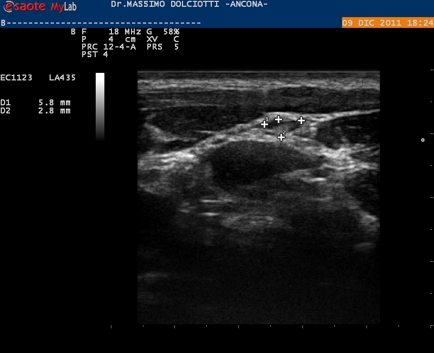

Ecografia del: 17/02/2012

Strumento: Esaote MyLab 50 Gold - Responsabile Linea Cardio Esaote Regione Marche Dr. Franco Fabi

Sonda: Lineare Multifrequenza 12-18 MHz

Età Paziente:  F 48 anni

Motivazione dell'esame: ferita da taglio al secondo dito della mano destra con lesione tendinea, occorsa 30 giorni prima.

Commento all'esame: le immagini ed il video documentano l'ispessimento e la disomogeneità del tendine estensore dell'indice della mano destra, con evidenza di immagini iperecogene in prossimità del tendine, da ricondurre a punti di sutura. Pressoché regolare l'estensione tendinea.

Conclusioni: lesione tendinea parziale in via di cicatrizzazione dopo sutura.